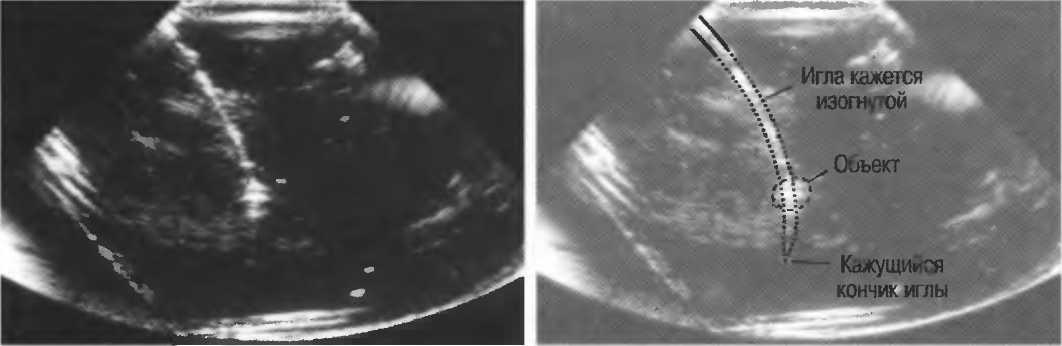

На практике, наиболее значимые в клиническом плане артефакты возникают при проведении биопсии или аспирации под контролем ультразвука. До тех пор пока кончик иглы не появится в плоскости сканирования на экране, он не будет визуализироваться, и может создаться ложное представление о том, что игла значительно короче (рис. 21в).

Рис.21 в. Изображение иглы в емкости с водой. Слева игла находится в плоскости сканирования не полностью, в результате чего выглядит короче, чем есть на самом деле (крестик определяет реальную глубину проникновения иглы). Справа игла визуализируется полностью.